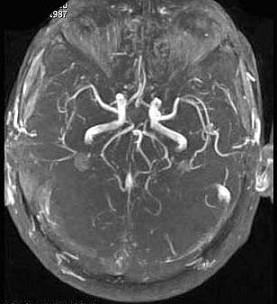

问题 男,35岁,头痛半年加重1周,左侧肢体无力,影像检查如图所示,最可能的诊断为()

选项 A.脑血管畸形 B.脑梗死 C.脑出血 D.脑炎 E.脑静脉性血栓

答案 E